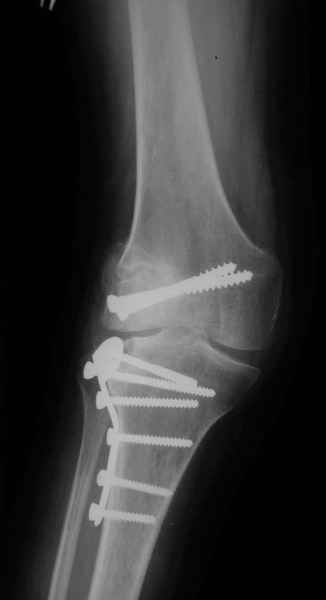

Как вариант решения прогрессирующей вальгусной деформации коленного сустава я бы предложил косую остеотомию дистального отдела бедра с фиксацией пластиной и компрессирующим винтом.

Взгляните на снимки , может быть это вам поможет.

Около 5 лет применяю этот тип дистальной остеотомии бедра для коррекции механической оси Н/К ( более 20 случаев) - достаточно эффективная операция.

Уважаемый Евгений ! Спасибо за ответ, но мне представляется, что в нашем случае основной проблемой является не столько прогрессирующий вальгус конечности, сколько несросшийся перелом мыщелка бедра и дефект мыщелка большеберцой кости - вероятно первичная репозиция выполнялась без пластики.

Тут ситуация совсем другая. Деформация не около-, а самая что ни на есть внутрисуставная. Покорректировать внешний вид конечности путем остеотомии дистального отдела бедра и high tibia (плюс или минус клин, одномоментно-постепенно, аппарат-пластина-стержень - дело третье) не сильно сложно, но это не решение проблемы. У больной, по

сути отсуствует латеральный отдел коленного сустава, что требует костно-пластических вмешательств непосредственно на артикулирующих

поверхностях.

Может быть, целесообразней сразу протез, чем тот же протез, но после сложных, но сомнительно результативных операций типа замещения алломыщелком, моделирующих резекций и т.п.? Ну и в любом случае движения лучше бы разработать получше до любой операции.